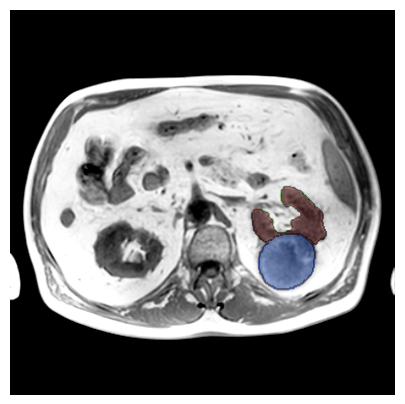

Purpose: To introduce a deep learning model capable of multi-organ segmentation in MRI scans, offering a solution to the current limitations in MRI analysis due to challenges in resolution, standardized intensity values, and variability in sequences. Materials and Methods: he model was trained on 1,200 manually annotated MRI scans from the UK Biobank, 221 in-house MRI scans and 1228 CT scans, leveraging cross-modality transfer learning from CT segmentation models. A human-in-the-loop annotation workflow was employed to efficiently create high-quality segmentations. The model's performance was evaluated on NAKO and the AMOS22 dataset containing 600 and 60 MRI examinations. Dice Similarity Coefficient (DSC) and Hausdorff Distance (HD) was used to assess segmentation accuracy. The model will be open sourced. Results: The model showcased high accuracy in segmenting well-defined organs, achieving Dice Similarity Coefficient (DSC) scores of 0.97 for the right and left lungs, and 0.95 for the heart. It also demonstrated robustness in organs like the liver (DSC: 0.96) and kidneys (DSC: 0.95 left, 0.95 right), which present more variability. However, segmentation of smaller and complex structures such as the portal and splenic veins (DSC: 0.54) and adrenal glands (DSC: 0.65 left, 0.61 right) revealed the need for further model optimization. Conclusion: The proposed model is a robust, tool for accurate segmentation of 40 anatomical structures in MRI and CT images. By leveraging cross-modality learning and interactive annotation, the model achieves strong performance and generalizability across diverse datasets, making it a valuable resource for researchers and clinicians. It is open source and can be downloaded from https://github.com/hhaentze/MRSegmentator.